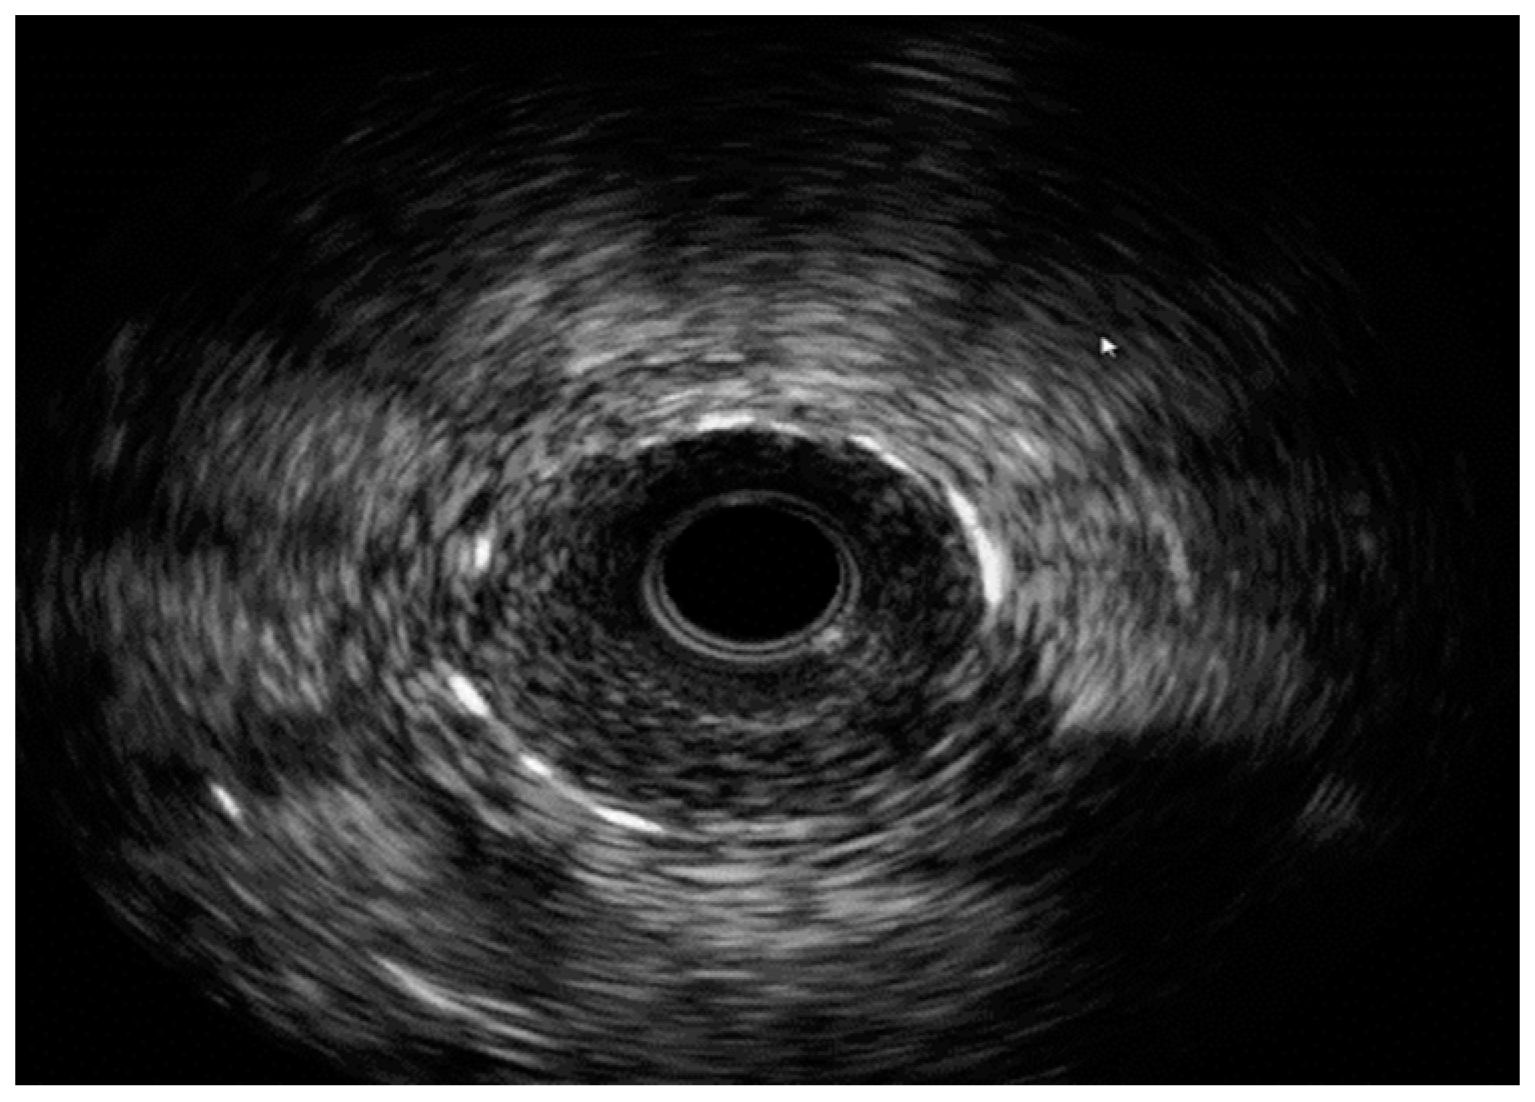

IVUS with severe ISR. Images are from author’s collection.